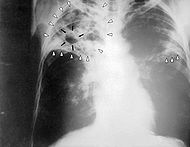

Туберкулёз

Туберкулёз (от лат. tuberculum — бугорок) — инфекционное заболевание человека и животных (чаще крупного рогатого скота, свиней, кур), вызываемое несколькими разновидностями кислотоустойчивых микобактерий — Mycobacterium tuberculosis (палочка Коха).

Клинические формы туберкулёза

Чаще всего туберкулёз поражает органы дыхательной системы (главным образом лёгкие и бронхи), однако возможно поражение и других органов. Ввиду этого различают два основных вида туберкулёза: туберкулёз лёгких и внелёгочный туберкулёз.

Туберкулёз лёгких может длительное время протекать бессимптомно или малосимптомно и обнаружиться случайно при проведении флюорографии или рентгеновском снимке грудной клетки. Факт обсеменения организма туберкулёзными микобактериями и формирования специфической иммунологической гиперреактивности может быть также обнаружен при постановке туберкулиновых проб

Далее по ходу развития заболевания присоединяются более или менее явные симптомы со стороны пораженного органа. При туберкулёзе лёгких это кашель, отхождение мокроты, хрипы в лёгких, насморк, иногда затруднение дыхания или боли в грудной клетке (указывающие обычно на присоединение туберкулёзного плеврита), кровохарканье. При туберкулёзе кишечника — те или иные нарушения функции кишечника, запоры, поносы, кровь в кале и т. д. Как правило (но не всегда), поражение лёгких бывает первичным, а другие органы поражаются вторично путём гематогенного обсеменения. Но встречаются случаи развития туберкулёза внутренних органов или туберкулёзного менингита без каких-либо текущих клинических или рентгенологических признаков поражения лёгких и без такового поражения в анамнезе.